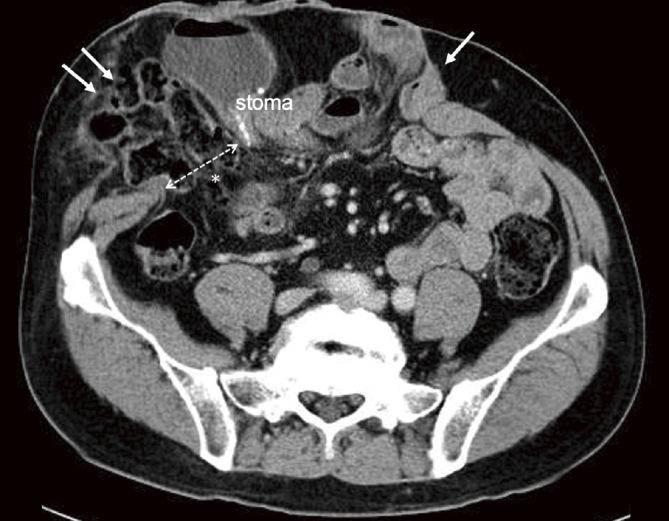

The comparison of patient backgrounds and hernia characteristics showed no significant differences between PCH and PICH groups. Surgical procedures included laparoscopic Sugarbaker repair (LSB) for PCH (29 cases) and PICH (8 cases), and endoscopic Pauli repair (ePauli) for both PCH (2 cases) and PICH (2 cases). Intraoperative findings indicated a significantly higher rate of severe intra-abdominal adhesions (Zühlke index III/IV) in the PICH group (60%) compared to the PCH group (23%) (p=0.0485). The median operation time was significantly longer for PICH (223 [120-423] minutes) than for PCH (158 [48-386] minutes) (p=0.0467). Perioperative complications occurred in 1 PCH case (3%) and 2 PICH cases (20%), with no significant difference in postoperative hospital stay (9 [4-19] vs. 9 [6-14] days). With the follow-up period of 57 [2-110] months for PCH and 52 [20-104] months for PICH, recurrence was observed in 4 PCH cases (12%) but not statistically significant.

患者背景和疝特征比较显示,PCH组和PICH组之间无显著差异。手术方式包括用于PCH(29例)和PICH(8例)的腹腔镜Sugarbaker修补术(LSB),以及用于PCH(2例)和PICH(2例)的内镜Pauli修补术(ePauli)。术中发现,PICH组(60%)严重腹腔内粘连(Zühlke指数III/IV)发生率显著高于PCH组(23%)(p = 0.0485)。PICH组的中位手术时间(223 [120 - 423]分钟)显著长于PCH组(158 [48 - 386]分钟)(p = 0.0467)。围手术期并发症在1例PCH患者(3%)和2例PICH患者(20%)中发生,术后住院时间无显著差异(9 [4 - 19]天对9 [6 - 14]天)。PCH的随访期为57 [2 - 110]个月,PICH为52 [20 - 104]个月,4例PCH患者(12%)出现复发,但无统计学意义。